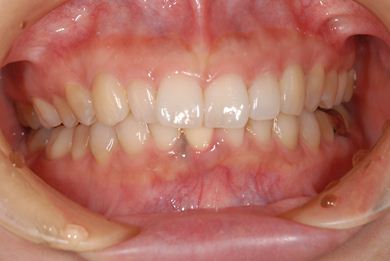

性別/年齢 女性 / 37歳

主訴 歯の差し歯が少しぐらつく。歯ぐきが違和感を感じる。

治療方針 抜歯と同時にインプラントを埋入し、治療期間を短縮する。

治療内容 インプラント1本(抜歯即日スピードインプラント)、メタルボンドセラミック1本

治療前

• 治療前